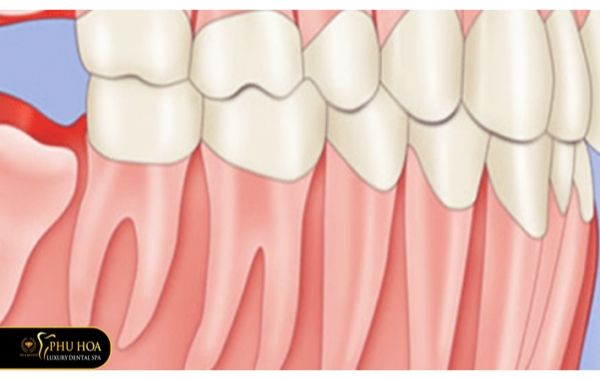

Răng khôn mọc lệch gần là khi răng số 8 mọc nghiêng về phía răng số 7 (còn hay gọi là nghiêng về phía trước). Khi trưởng thành xương hàm đã hoàn thiện và khi răng số 8 mọc thì không còn đủ chỗ để phát triển bình thường nên chúng sẽ mọc lệch. Đối với răng số 8 mọc lệch gần sẽ gây ảnh hưởng đến răng số 7, có thể xô gây tổn thương cho răng số 7 cũng như làm lệch cung hàm.

Nếu như răng khôn mọc gần thì nó sẽ tựa gần vào răng số 7. Còn răng khôn mọc xa, chân răng số 8 sẽ gần sát với chân răng số 7 nhưng đổ về phía trước chứ không đổ về phía răng số 7. Hậu quả của việc răng khôn hàm dưới lệch xa cũng là gây đau đớn, ảnh hưởng các răng liền kề.

Lúc này răng khôn giống như bị ngã rạp, nó không có điều kiện mọc thẳng đứng mà phải mọc ngang, tạo thành một đường thẳng đâm trực tiếp vào má hoặc ở phía dưới miệng gây đau đớn cho người bệnh. Răng khôn hàm dưới nằm ngang ngầm trong xương lúc bắt đầu mọc sẽ có ít dấu hiệu để người mọc răng khôn nhận biết. Nếu như để lâu thì răng khôn nằm ngang sẽ gây tiêu xương dẫn đến tạo thành nang và có thể biến thành u ác tính, rất nguy hiểm.